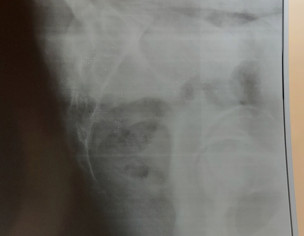

I have pain in my tail bone. Now I have when I sit or stand or lay on bed. Doc said its inflammation HISTORY--> tailbone was injured by falling 2 times at the same spot 5 years ago. I had that similar pain always while sitting or standing for long time but now it has increased n its very painful cant sit in my class. XRAY ATTACHED Thank you in advance